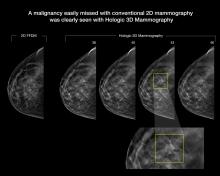

A major new study presented at the annual meeting of the Radiological Society of North America (RSNA) found that digital breast tomosynthesis, also known as 3-D mammography, has the potential to significantly increase the cancer detection rate in mammography screening of women with dense breasts.